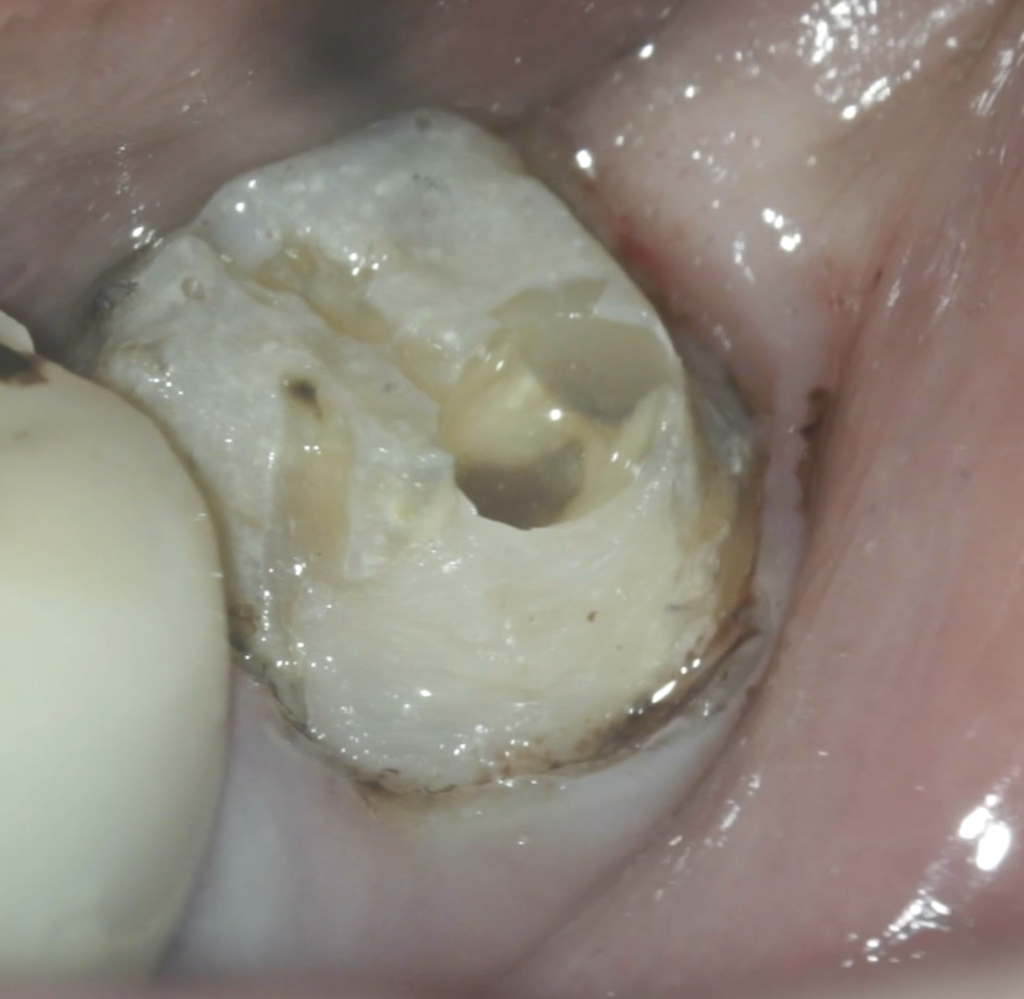

#18 RCT(2025.12.4)

除冠し当該部位を削ると…

既に虫歯が縁下にまで及んでいた。

これが主訴(左下奥がうずいたり、歯磨きをするときに痛い…食事をするときにも痛い。痛みが強くなると顎まで痛みが出ることがある…)の原因だったのだろう。